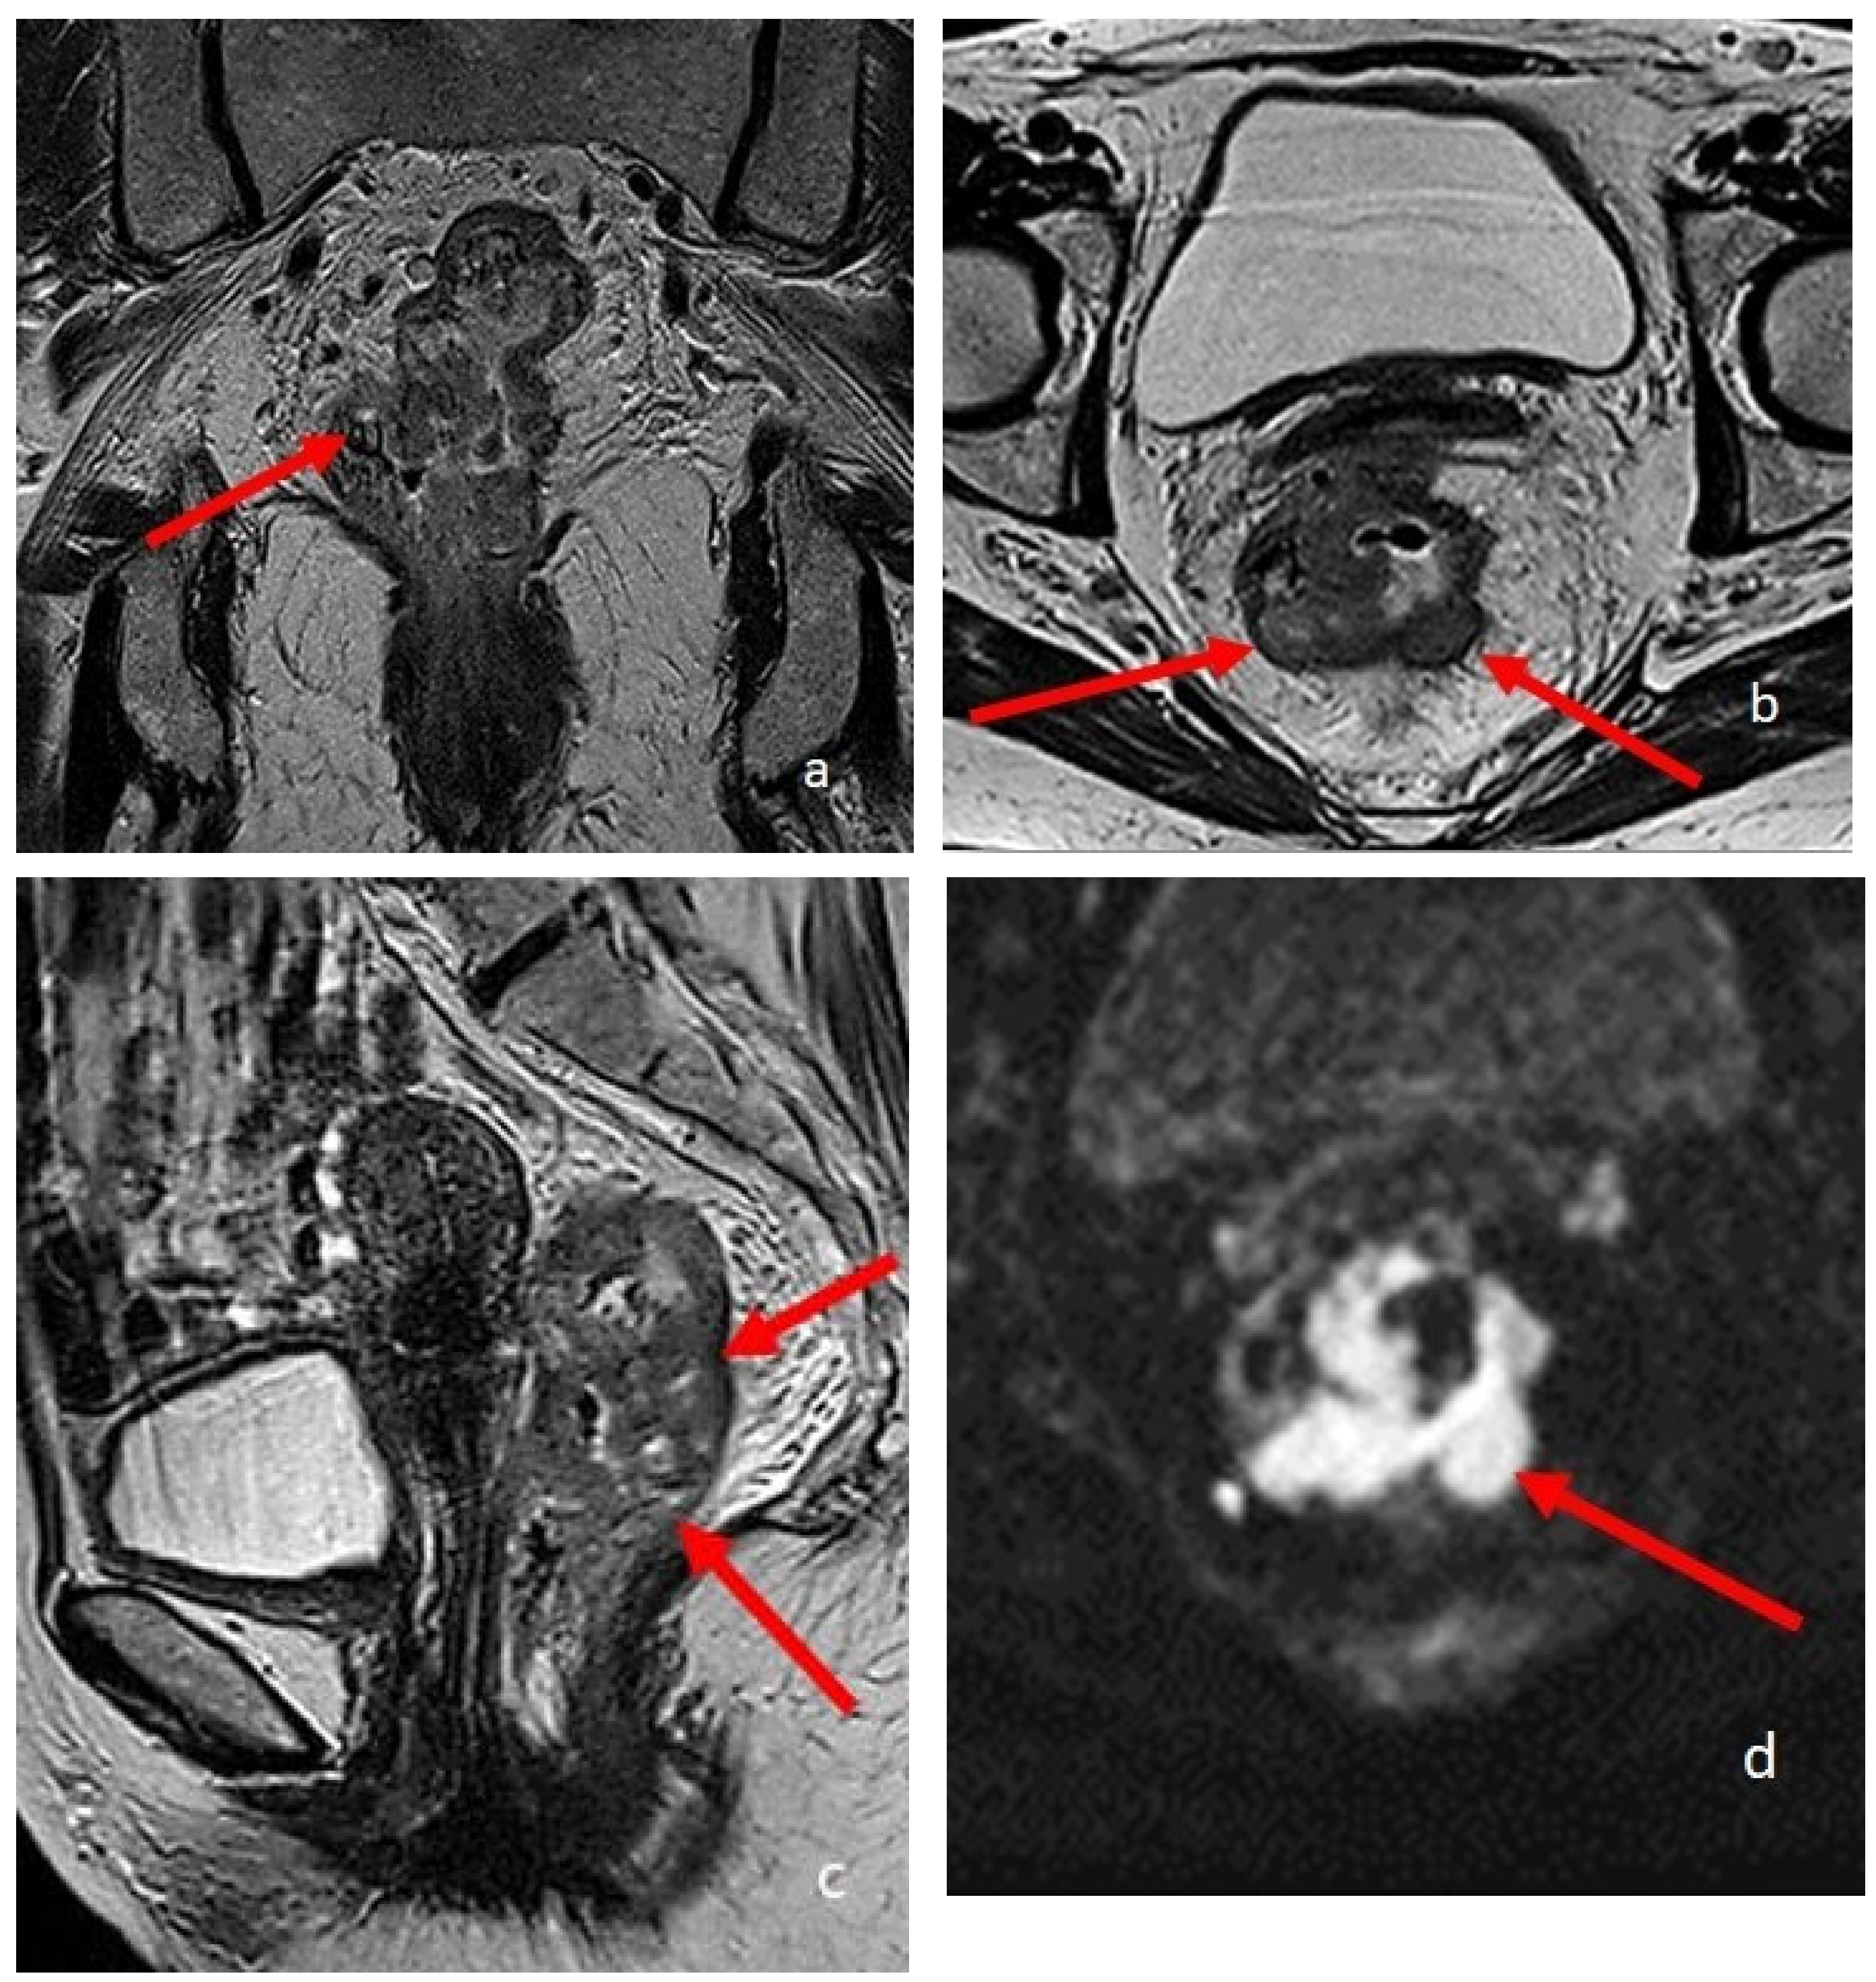

Figure 2.

An eighteen-year-old patient with Crohn’s disease; the arrows point to the wall involvement of the last ileal loop and caecum with wall thickening, post-contrast enhancement, and restricted diffusion. (a) is a coronal TrueFISP image; (b) is a coronal contrast-enhanced T1 weighted image; and (c) is an AxialT2 W high-resolution BLADE image. (d) Axial DWI b800.